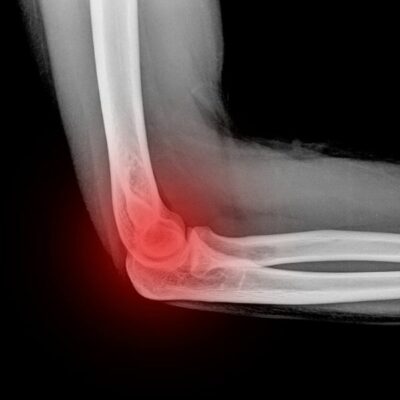

Any joint in the body is susceptible to arthritis, even the elbow. Meaning “inflamed joint” arthritis of the elbow occurs when the cartilage surface is worn or damaged and causes pain. For many people, arthritis of the elbow can cause pain not only when they bend their elbow, but also when they straighten it. Elbow specialist, James Mazzara, MD helps patients in Manchester, South Windsor, Enfield, Glastonbury and surrounding Hartford communities who suffer with this painful condition.

Dr. Mazzara will conduct an initial history review and physical examination to determine the areas of pain and tenderness as well as motion of the joint. X-rays may be needed to confirm the diagnosis.